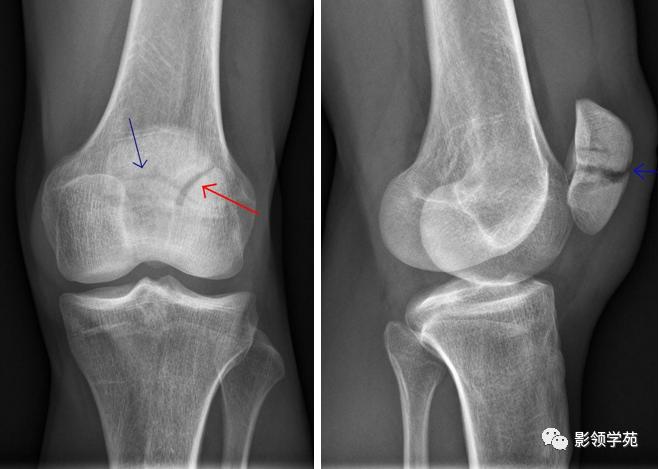

case1

先天性髌骨畸形,有髌骨缺如、小髌骨、二分髌骨、三分髌等类型。髌骨是人体中最大的籽骨 ,在出生时完全为透明软骨构成 ,2~5 岁时出现骨化中心 ,17~18 岁骨化完成 ,髌骨一般只有一个骨化中心 ,但有时可以有一个或数个次级骨化中心 ,在 10~14 岁时出现,次级骨化中心一般在 15 岁左右即愈合。二分髌骨乃少年阶段髌骨发育异常 ,出现1 个或 2 个副骨化中心 ,常见于髌骨外侧髌骨上1/ 4、外1 /4, 且常呈双侧对称发生, 而发生在中部的, 分左右或上下贯通的较为少见,个别在骨发育成熟后仍不与主骨融合。

二分髌骨

二分髌骨常位于髌骨外上角

透亮线边缘略显宽而不锐利、不移位。

侧位见透亮线位于髌骨后缘不是前缘(一般骨折多在前缘)。

髌骨骨折, 根据外伤史、局部压痛、髌骨异常活动、骨擦音及x 线辅助检查, 较易鉴别。